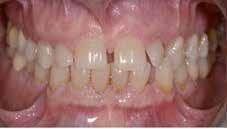

Hölgy páciensem az első konzultáció során tipikus kórtörténetet vázolt fel: Gyermekkora óta szeretett volna fogszabályozó készüléket, hiszen mindig is zavarta a class 2-es eltérésnél tipikusan jellemző nagy overjet (1-3. képek), és természetesen az ezáltal kifelé álló felső metszőfogai, részben a felső metszők protrúziója, részben pedig a disztálisan elhelyezkedő mandibula miatt. Annak ellenére, hogy több fogszabályozó szakorvosnál is járt az évek során, de mivel saggitális eltérése és az alsó metszőfogak torlódása miatt négy kisőrlőfog extrakcióját, illetve emellett sokszor állcsont műtétet is javasoltak neki, nem vágott bele a kezelésbe (4-5. képek).

A fogorvosa – nagyon helyesen – felhívta a figyelmét, hogy parodontális státusza is valószínűsíthetően romlani fog az eltérése miatt, újabb kört futott, immár 39 évesen, de még mindig premoláris fogak húzása és állcsontműtét nélkül szerette volna a fogszabályozást.

A konzultáció során arról is beszéltünk – ahogy az ilyenkor lenni szokott –, sohasem szeretett igazán mosolyogni, de a Pitts Protokolloknak köszönhetően az arc- és mosolyesztétikai céloknak megfelelően kerül megvalósításra az okklúziós korrekció. Az okklúziós kezelési célok az alábbiak voltak: a felső és alsó fogív nivellálása és tágítása, az alsó fogsor/ mandibula mezializálása, valamint a harapás megemelése által a mélyharapás rendezése.

A fogkontúrálás és az interproximális redukció alkalmazásával a mikroesztétikai részletek tökéletesítése is megtörtént (11. kép) A kezelés mindössze 16 hónapig tartott, megtörtént a rágófunkció helyreállítása, és az esztétikai végeredmény sokéves várakozás után valóban fordulópontot jelentett páciensünk életében (12-14. képek).